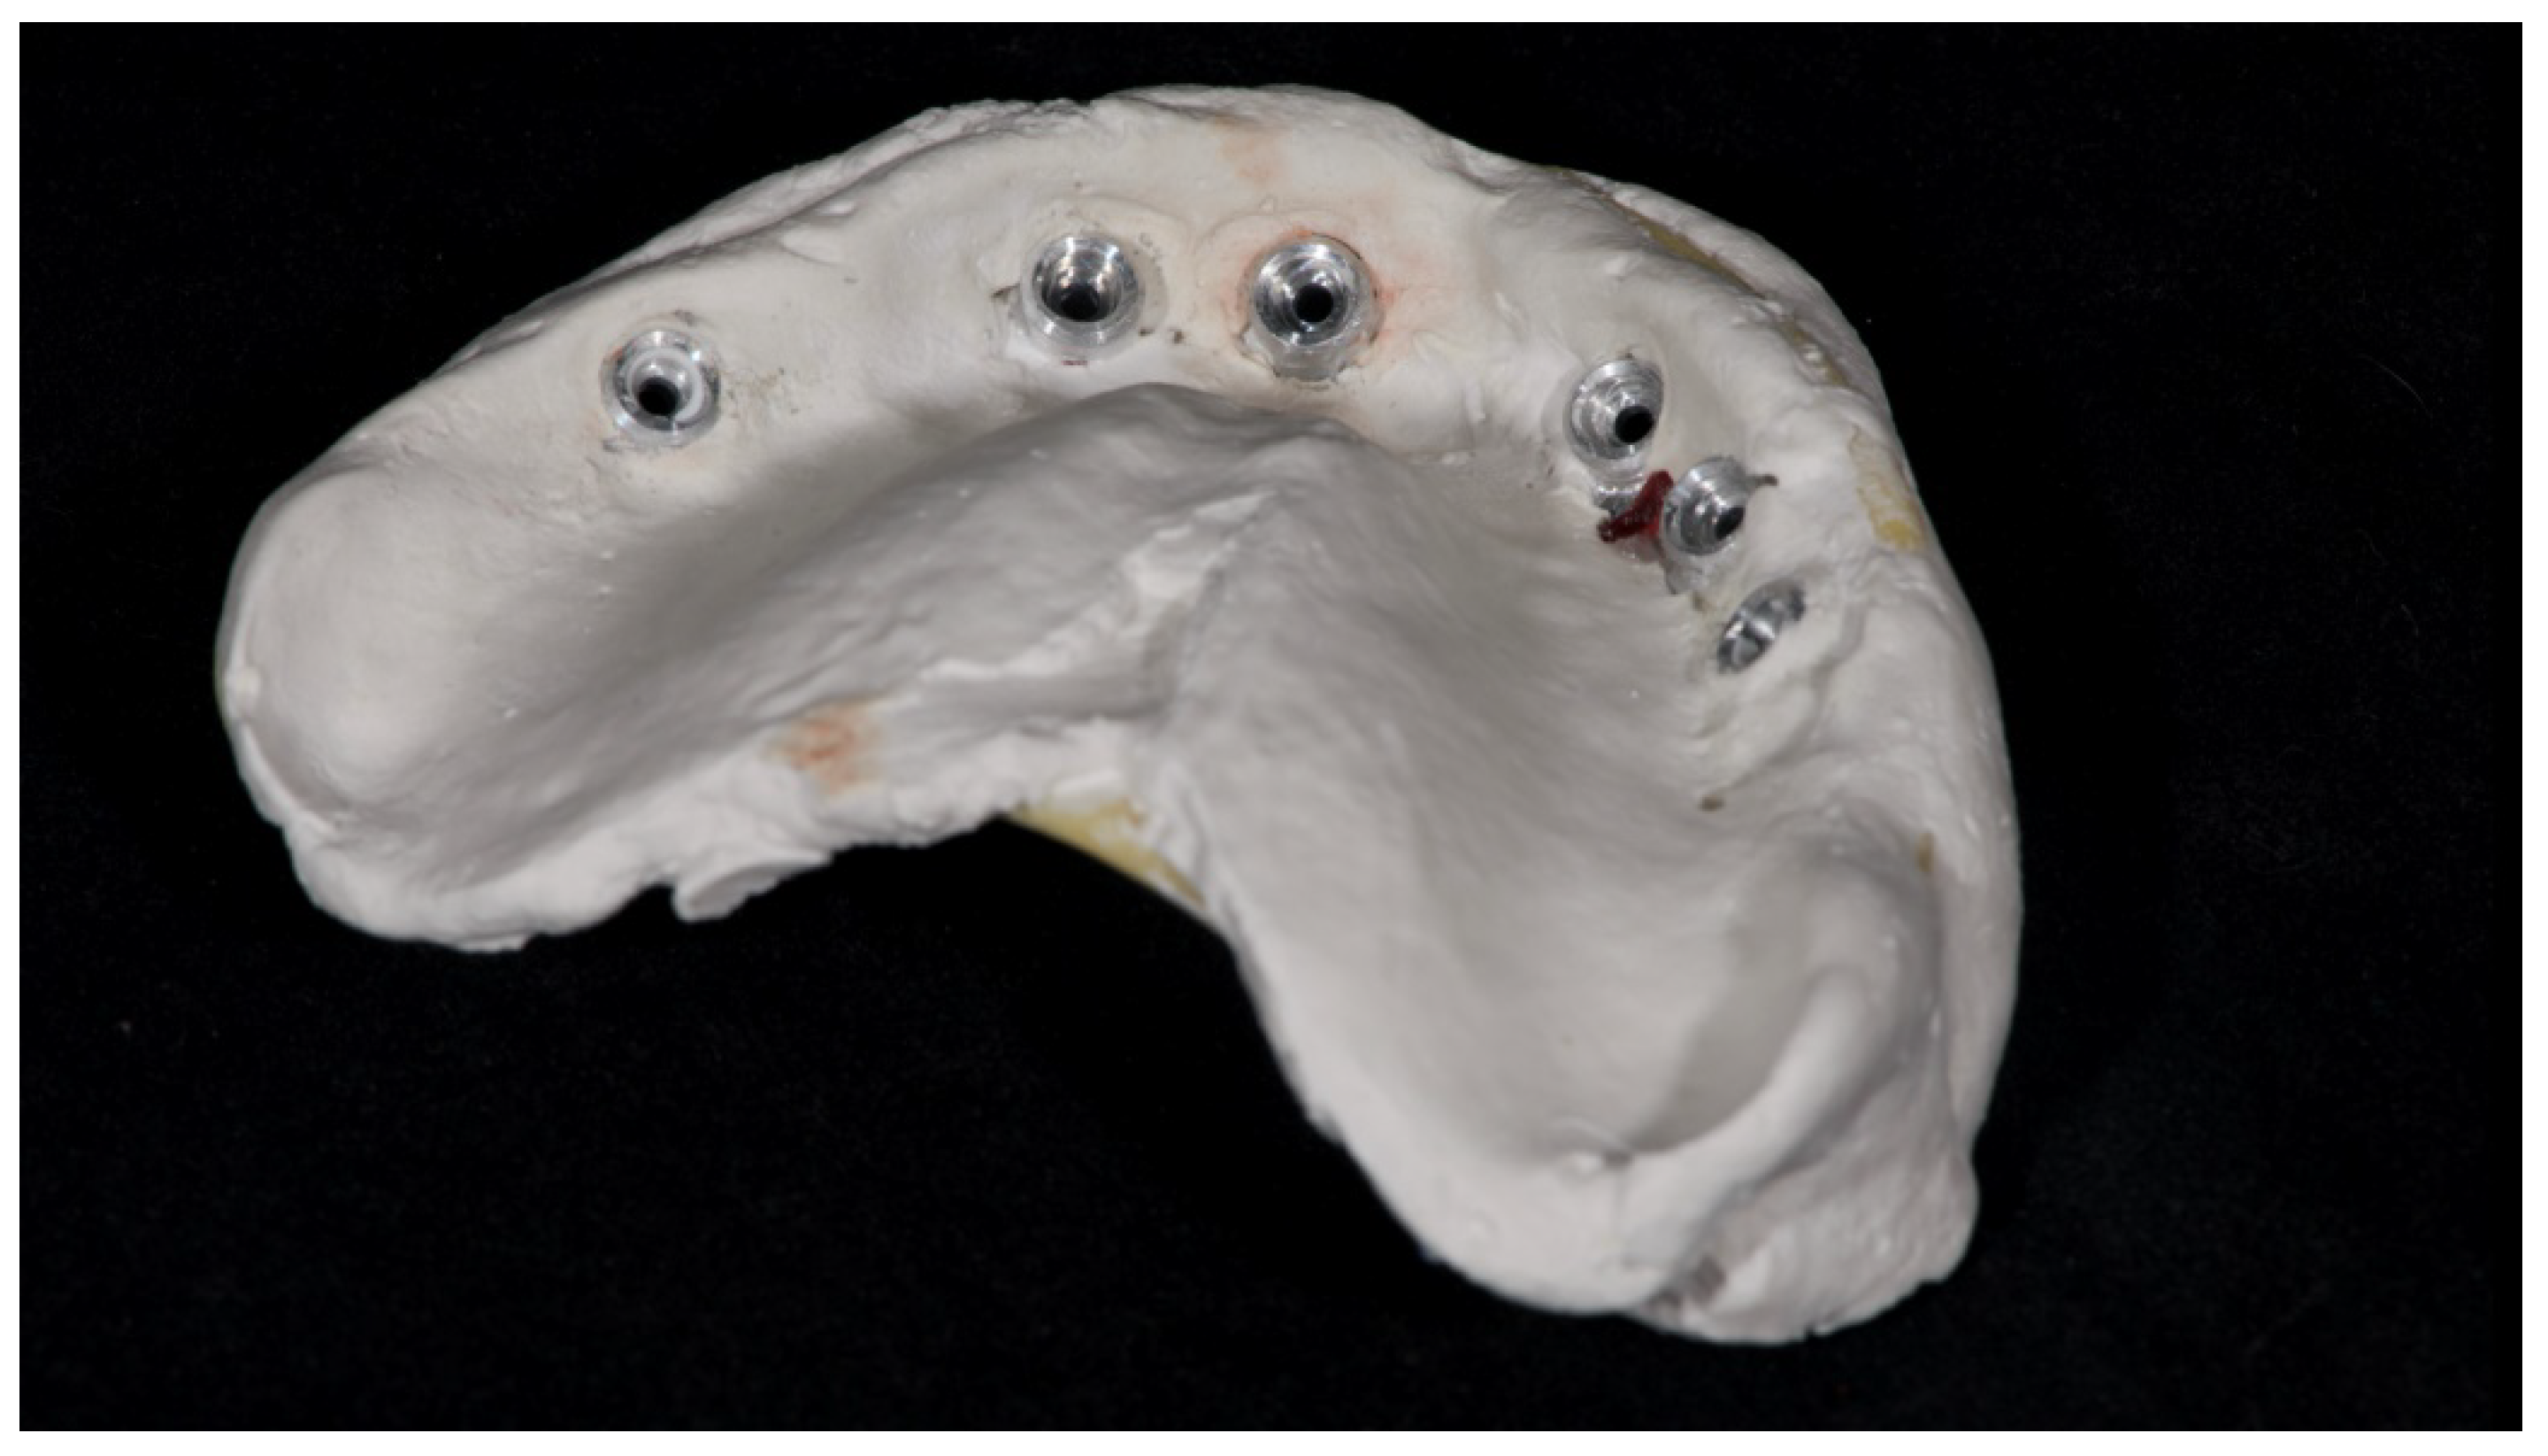

Figure 9.

Internal detail of the plaster impression.